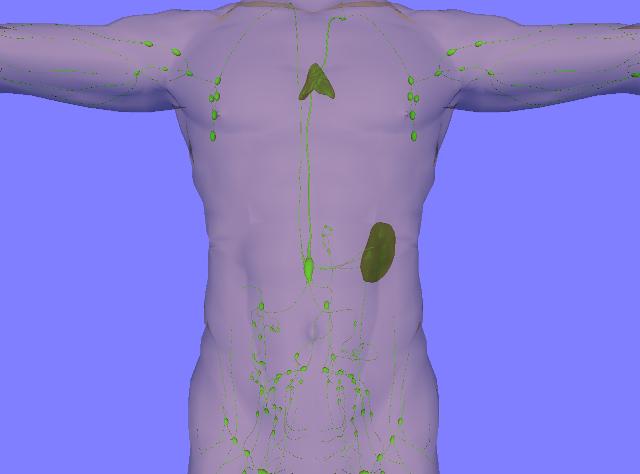

Изображения и схемы: как выглядит лимфа